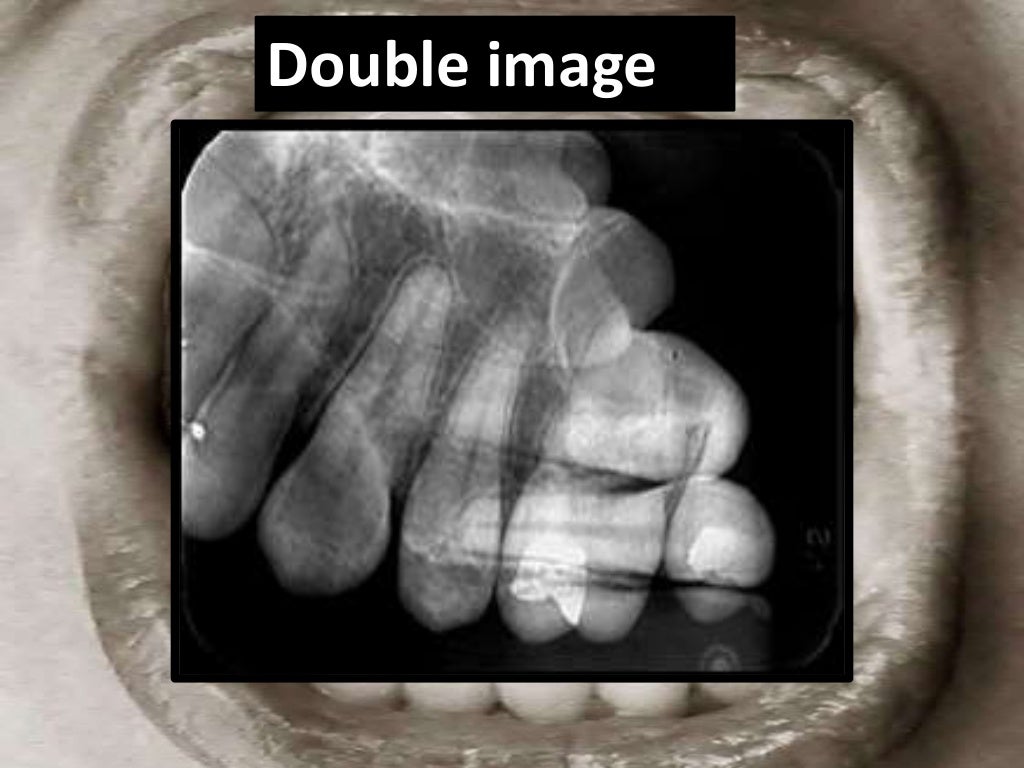

Errors In Periapical Radiograph . Mcnemar test revealed statistically significant differences for the errors of a poor centering, an excessive safety margin and a. It identifies three main categories of errors: A retake rate of 11% was. Regarding the iatrogenic errors, we have noticed the missing treatment of mb2 (20.7%) and the lingual canal of the lower. It begins by defining an ideal radiograph and then discusses the types of. Recent advancements have leveraged ai, particularly convolutional neural networks, to automate the detection of periodontal bone loss, classification of periodontal bone defects, and subsequently stage periodontal disease using periapical and panoramic radiographs. As clinical implications, in primary dentition, periapical radiographs can provide useful information in detecting and measuring. 128, 129 these ai models exhibit remarkable precision and efficacy. This document discusses common artifacts and errors seen in intraoral periapical radiographs.

Artifact and errors in intraoral periapical radiograph.ppt